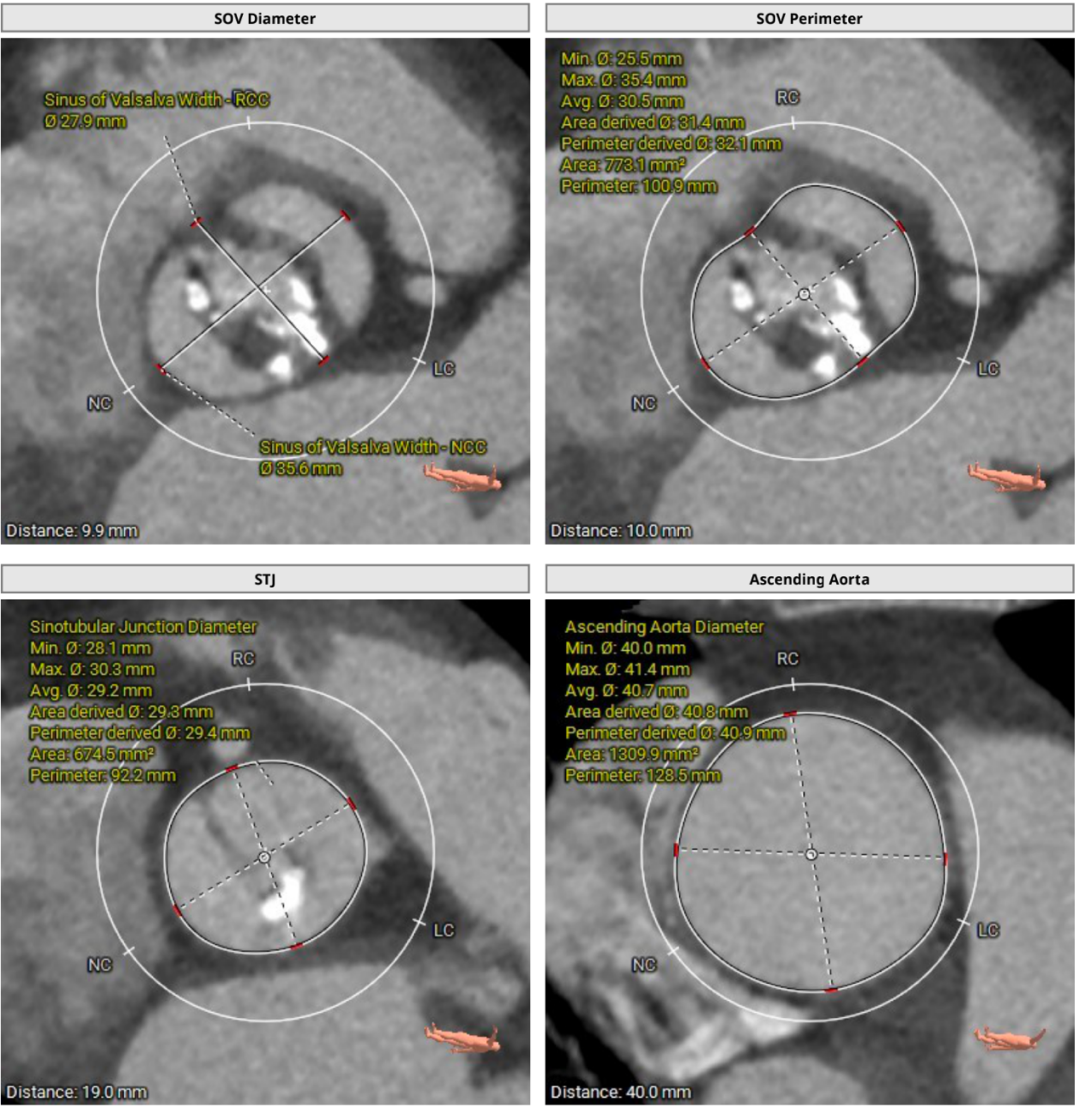

3.瓦氏窦、窦管交界内径正常,升主动脉扩张;左室腔内径可,心室壁增厚;

主动脉根部测量

瓣上结构测量

随着TAVR技术在国内的普及,主动脉瓣狭窄患者有了更多的治疗选择。本例患者为主动脉瓣重度狭窄伴轻度反流,患者伴代偿性心力衰竭,术前评估适宜行TAVR手术,有TAVR手术指征。术前CT分析提示患者为Type0型二叶式主动脉瓣,瓣环径23.5mm,瓣叶增厚伴重度钙化,钙化主要分布于无窦与左窦交合缘及瓣叶边缘,LVOT呈类直筒状形态,预估人工瓣膜会有较明显形变,有根部撕裂、损伤风险。左室流出道可提供辅助锚定,综合预估瓣膜锚定定位精度要求较高。患者又为横位心,主动脉弓距及夹角尚可,升主动脉扩张,需警惕血管夹层、破裂等风险,对经导管主动脉瓣输送系统过弓、跨瓣的性能要求较高。综合以上因素,该患者行TAVR手术对术者快速、精准的操作能力及手术团队的密切配合要求较高。广东省人民医院赣州医院(赣州市立医院)倪忠涵院长带领团队,经过心内科、心外科、麻醉科、超声等多学科团队的缜密讨论,最终决定为患者施行TAVR手术治疗。